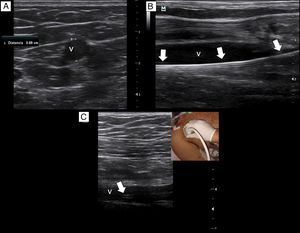

Briefly, with a tourniquet high in the arm, we scan for target veins based on their patency, size and depth. Patent veins with a diameter ≥4mm and closest to the skin are only considered for cannulation (Fig. 2a). Basilic vein of the arm, a brachial vein or the cephalic vein of the arm typically fulfill these criteria. For catheter placement, aseptic technique and maximal sterile barrier precautions are used. We perform the in-plane technique in all the cannulations. As in our institution there are no available kits of MC, we replace it by a central venous catheter kit (polyurethane-based, 14-16G, 20–30cm in length catheters). After inserting the needle by dynamic ultrasound guidance, blood is freely aspirated and guidewire is then passed, we confirm that the latter is in the vein lumen before passing the dilator (Fig. 2b). When introducing the catheter, to avoid advancing in the subclavian vein, we check by ultrasound that the catheter tip lies in the thoracic tract of the axillary vein (Fig. 2c). To avoid dislodgement of the catheter, we secure it by suturing both the holding clips and the hub to the skin.